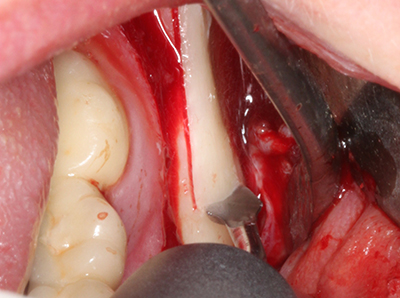

Abb. 28: Im Rahmen der Metallentfernung erfolgt die Abtrennung der basalen Kinnanteile unter Beibehaltung der lingualen Blutversorgung mit dem Piezomed.

Abb. 29: Vorverlagerung des Kinns um 5 mm und Fixierung mittels zweier Osteosyntheseplatten (KLS Martin). Im Randbereich sind beide Nn. mentalii zu erkennen.